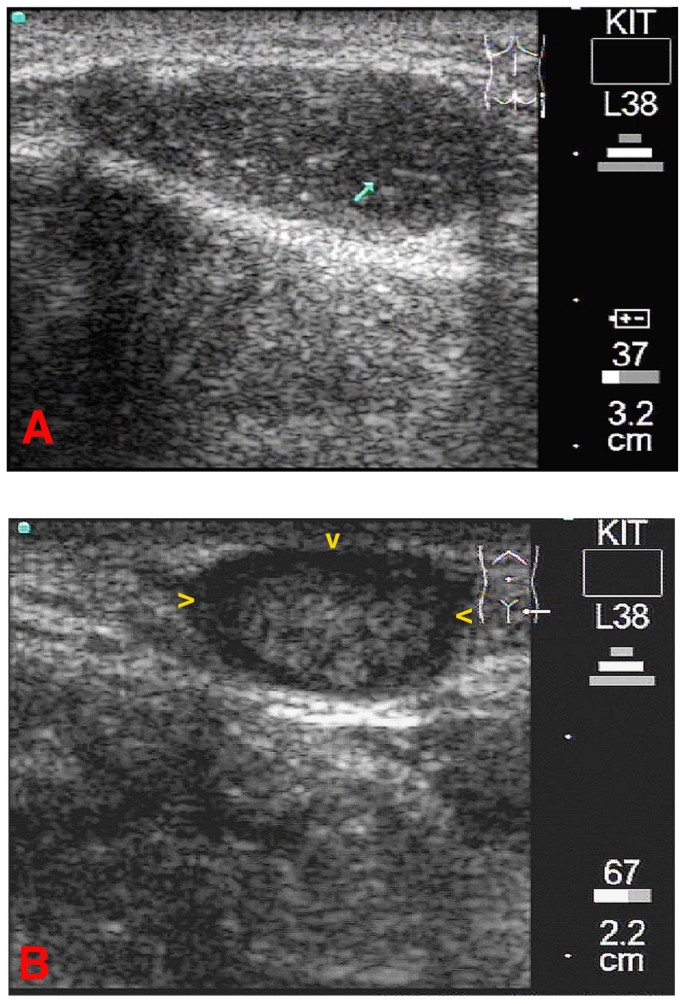

Figure 1

1A: Longitudinal scan of the patient's right iliac crest. The b-mode image shows a small subcutaneous onchocercoma. Measurement is shown in the largest transverse and longitudinal section of the nodule. In this homogenous onchocercoma no worm movements were detected. 1B: Longitudinal scan of the crena analis. A medium sized homogenous subcutaneous onchocercoma can be seen. As in image 1A no worm movements were detected. A differentiation of worm centre, corresponding to a coil of worms, from the capsule was not possible in this nodule. A lateral shadow is visible on both sides of the onchocercoma (yellow arrowheads)